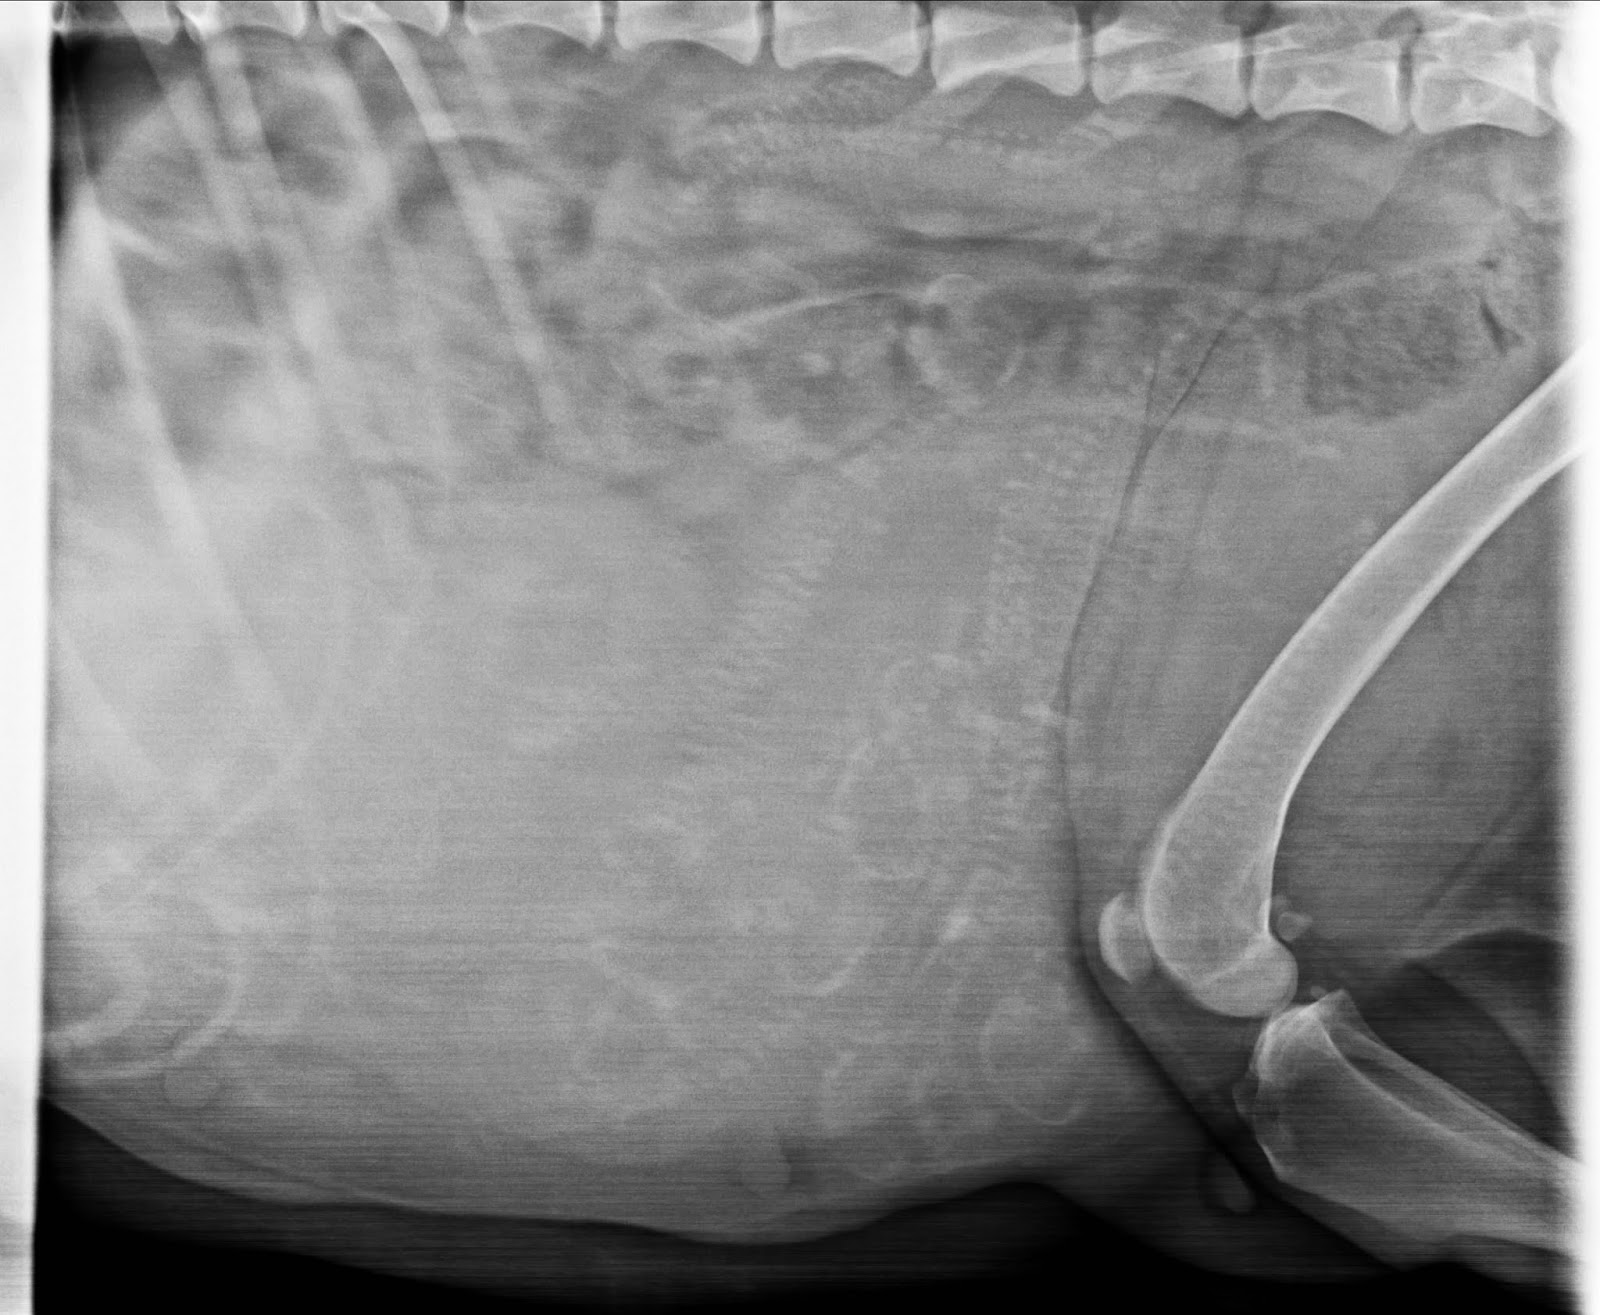

No, niin! Vickanin sisuksiin kurkattu ja kuva tulee tässä. Laskentatehtävä on haasteellinen, koska kaikki luurangot olivat valahtaneet samaan kasaan. Jouduttiin menemään toiselle eläinlääkärille. Hän otti yhden kuvan ja siitä sitten yritettiin laskeskella.

Oma ell on ottanut useamman kuvan, jotta löytyy se paras mahdollinen, mistä laskea. Näin tällä kertaa. Harmittaa vähän, mutta hyvä, että saatiin kuitenkin kuva aikaiseksi :)